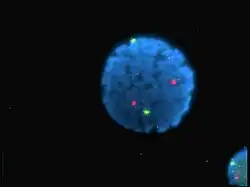

Esta tecnología es particularmente importante en el campo de la bioquímica y de los estudios sobre proteínas, por ejemplo en inmunofluorescencia e inmunohistoquímica; o en el análisis de ADN, mediante la técnica de PCR en tiempo real.

El isotiocianato de fluoresceína, un derivado reactivo de la fluoresceína ha sido uno de los fluorócromos que más habitualmente se han unido químicamente a otras moléculas no fluorescentes para generar nuevas moléculas fluorescentes para las más diversas aplicaciones. Otros fluorocromos que han sido comunes a lo largo de la historia son los derivados de la rodamina, cumarina y cianina. La nueva generación de fluorocromos como el Alexa Flúor o los DyLight Flúor son generalmente más fotoestables, brillantes y menos sensibles al pH que otros colorantes estándar de excitación y emisión comparable.